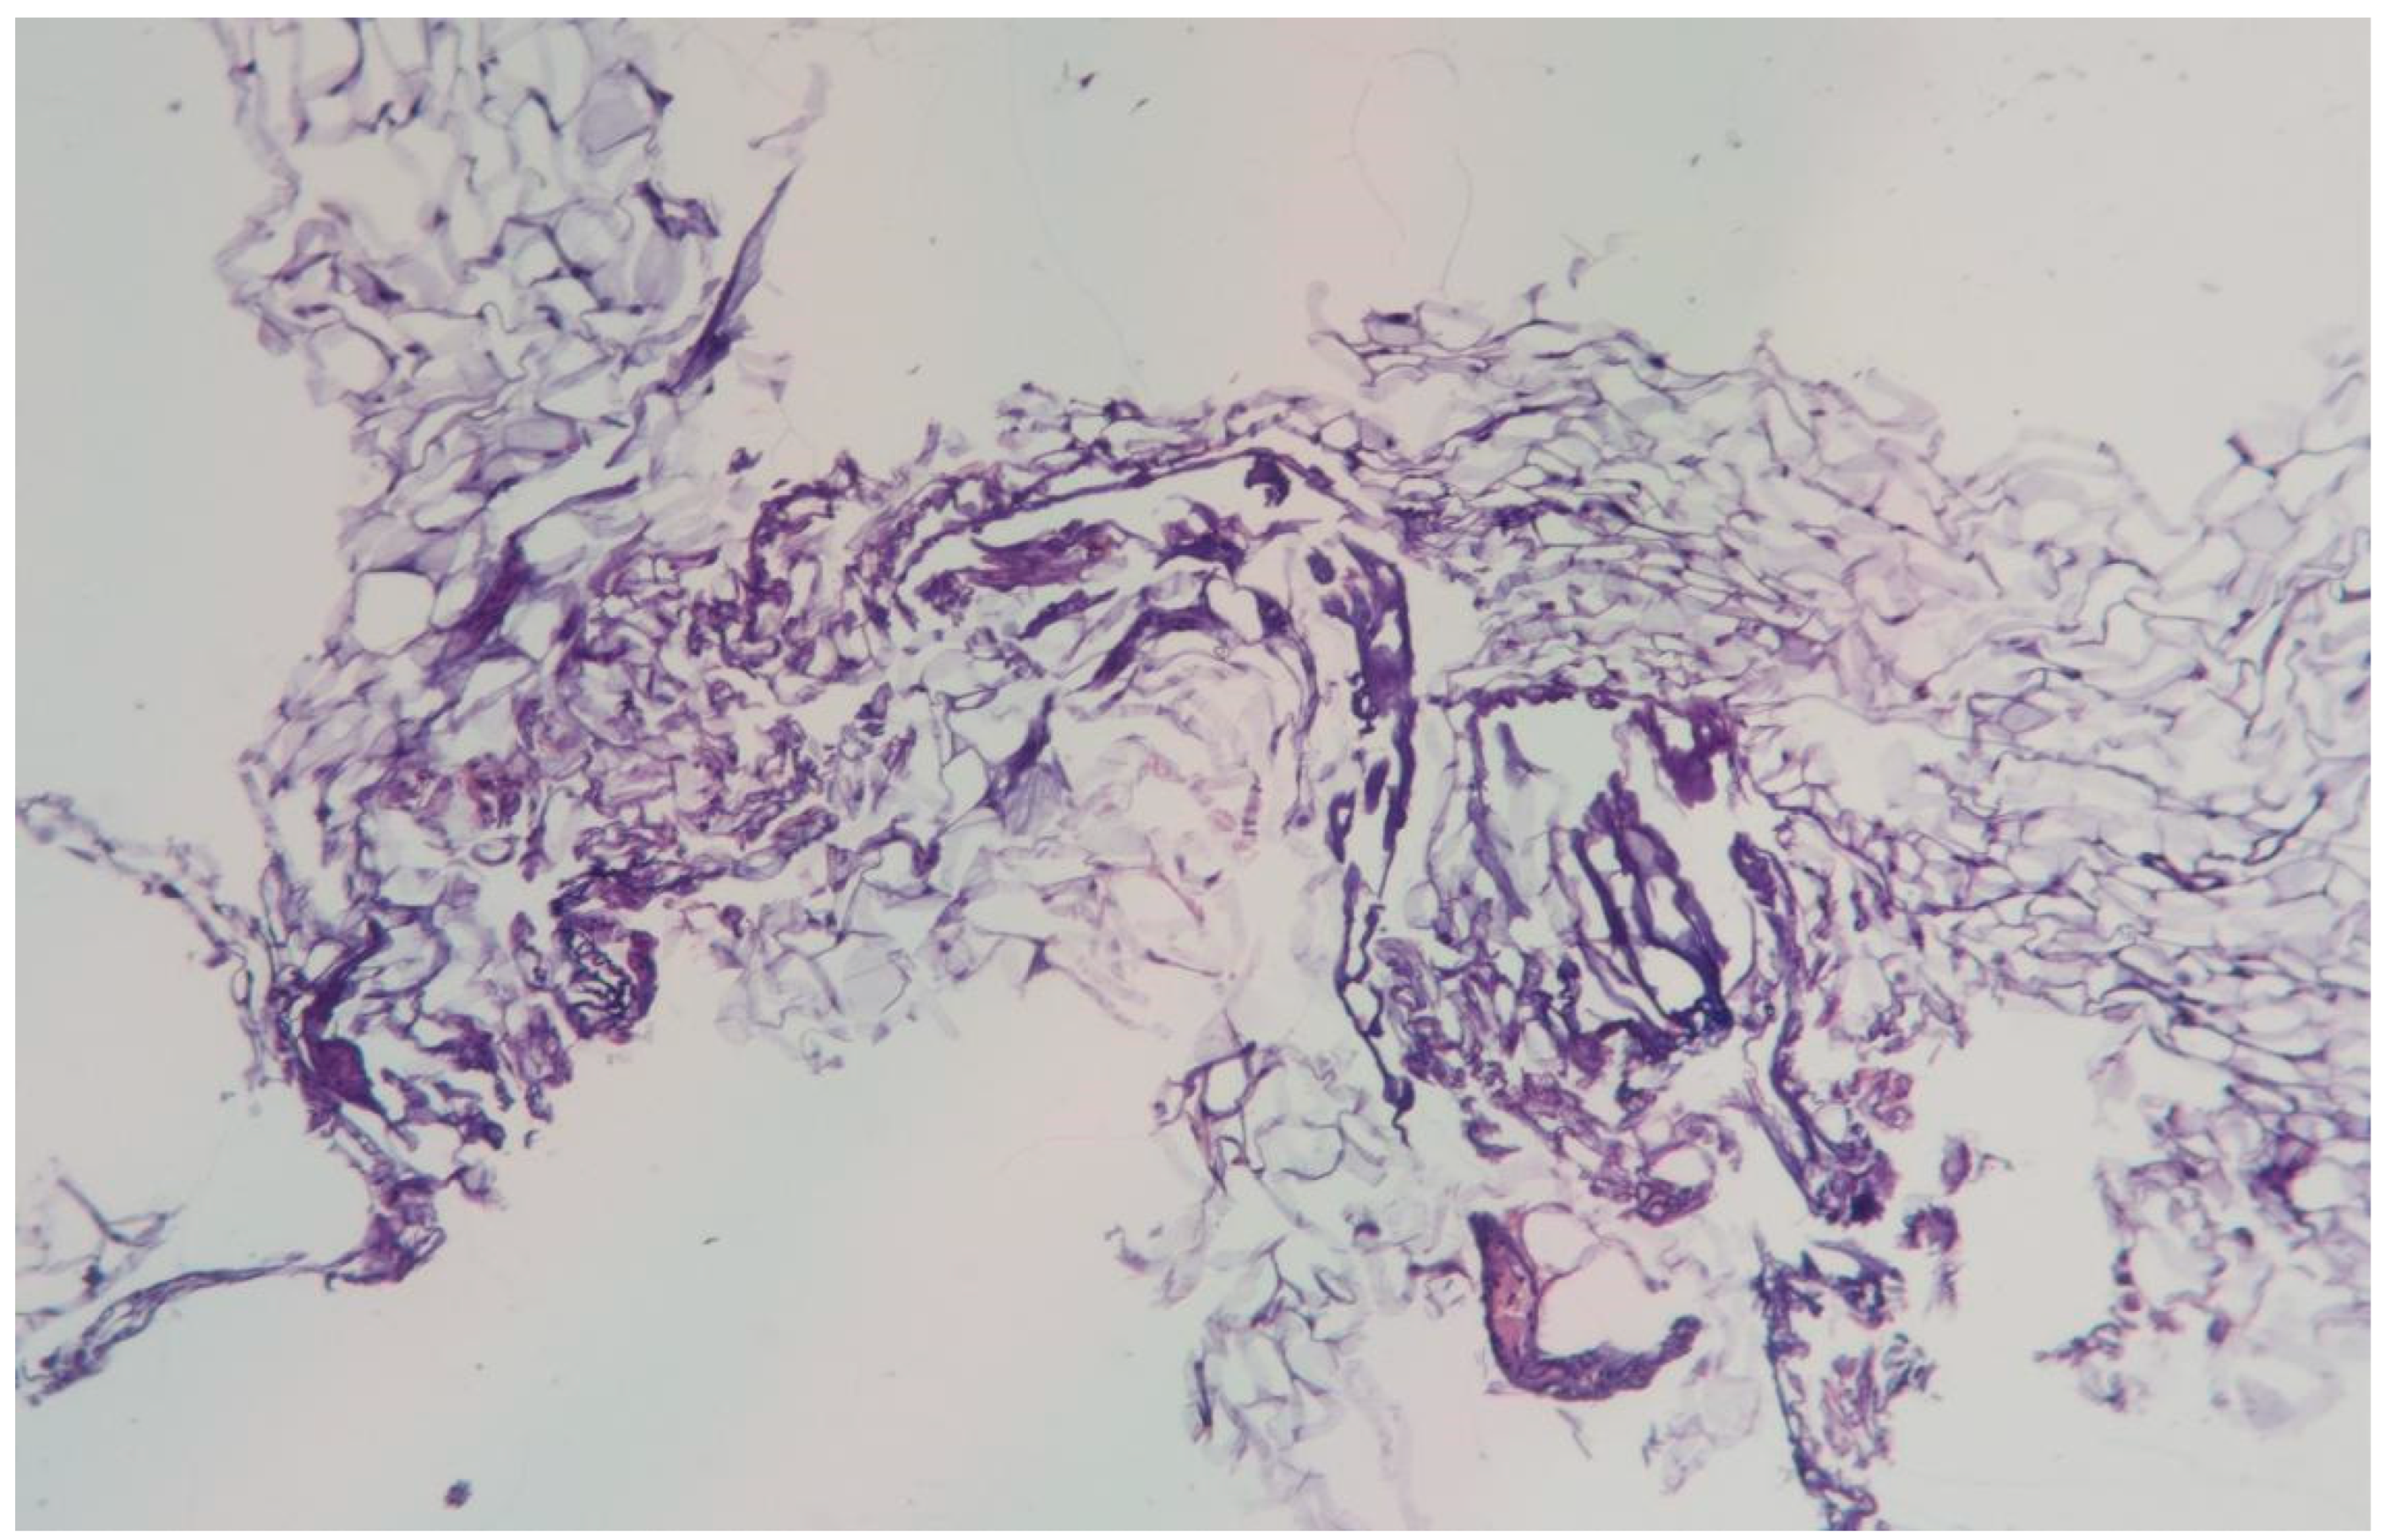

3.1.3. Clinical Case 3: Soft Tissues in the Dissection Area, Scar 20 W (See Figure 4)

Description: The histological examination showed preserved epidermis and underlying dermis. The vessels of the superficial vascular plexus were dilated, while those of the deep plexus collapsed. There was noted collagen fiber densification at the biopsy edge. No inflammatory changes were observed, and the skin appendages remained intact.

Figure 4. Skin changes in Rat 1 on the 7th day after exposure to the thulium laser at 20 W, 100 Hz. H&E staining, 10× objective magnification.

On the 7th day after exposure to the thulium laser at 20 W, the tissues were almost completely restored, with scar tissue formation characterized by slightly densified collagen fibers.